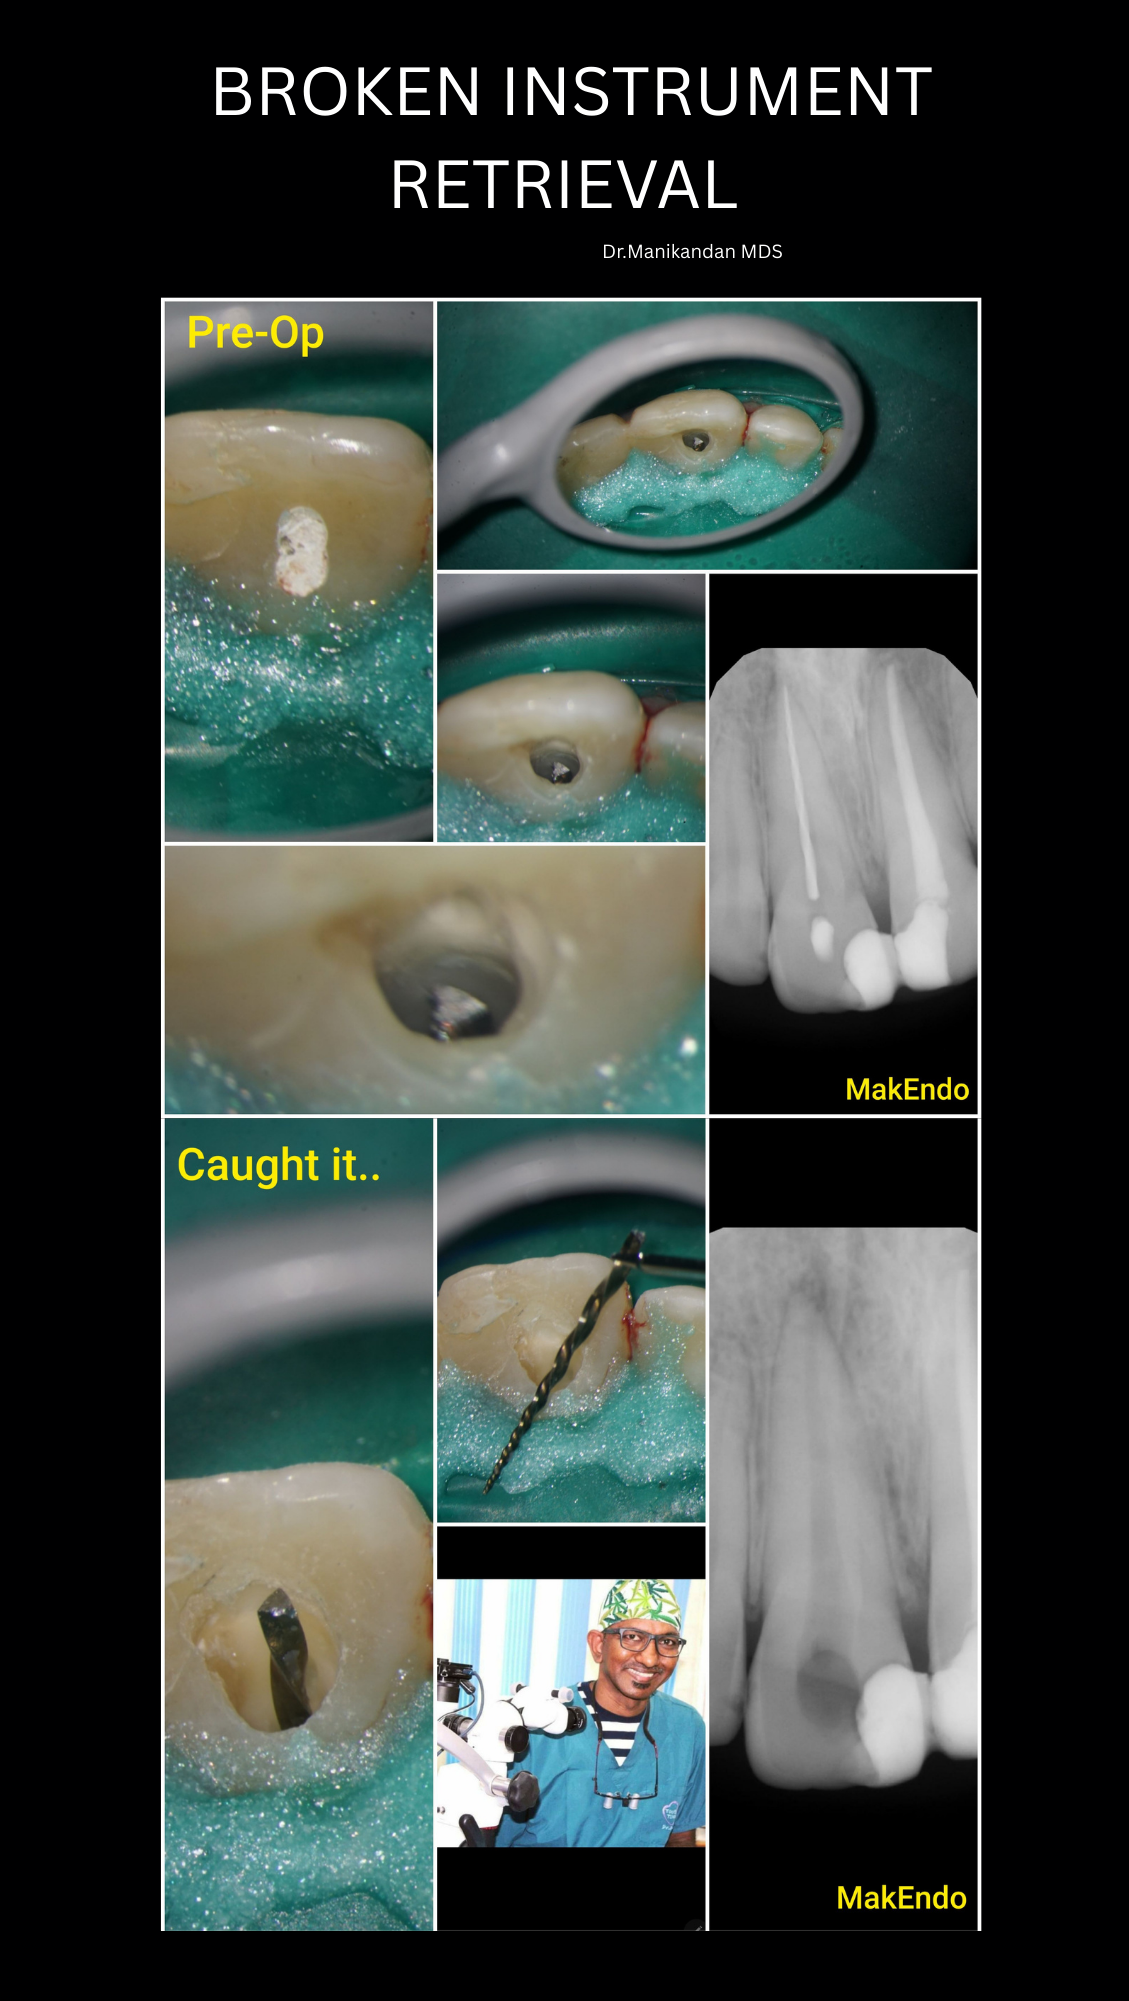

Our clinic specializes in Root Canal Treatment under a Microscope, a state-of-the-art procedure that ensures precision, comfort, and long-term dental health. Led by the highly experienced Dr. Manikandan, we bring expertise, advanced technology, and compassionate care to every root canal procedure.

With over 25 years of experience, Dr. Manikandan is a specialist in root canal therapy. His meticulous approach and expertise in microscope-assisted procedures ensure patients receive the best possible care. Known for his gentle techniques and attention to detail, Dr. Manikandan has built a reputation as one of the best dentists in Coimbatore.

Our clinic is equipped with the latest dental technologies, including high-powered dental microscopes, which enhance visibility and precision during root canal treatments. This ensures successful outcomes even for complex cases like curved or calcified canals.

Our modern dental microscopes allow detailed visualization of the root canals, ensuring thorough cleaning and sealing for optimal results.

We use advanced imaging technologies to assess the internal structure of the tooth, aiding in accurate diagnosis and treatment planning.